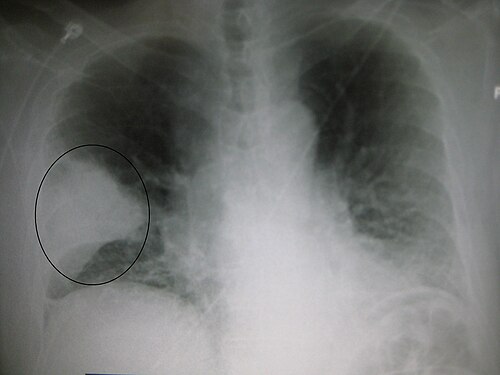

肺炎